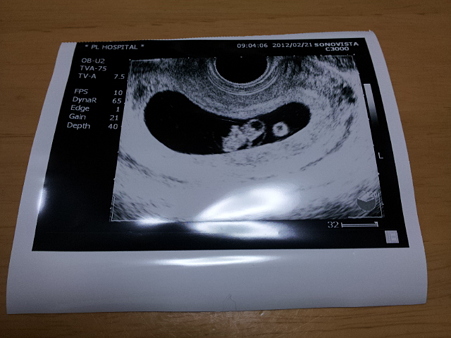

2012-02-22 00.08.14 (C)takaak                    嫁さんが妊娠3ヶ月になりました。優生は秋にお兄ちゃんになります。誰に似たのか世話焼きなので赤ちゃんの面倒を見てくれるでしょう。

まだ性別は分かりませんが、優生曰く女の子だそうです。ほんとかな?(((^_^;)